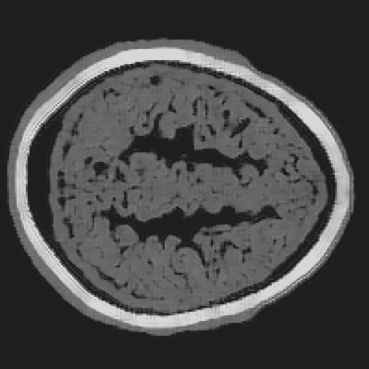

Refer to caption

(a) RCAN.

(b) LDM.

(c) ViT.

(d) BrainPuzzle.

(e) Ground Truth.

(f) RCAN.

(g) LDM.

(h) ViT.

(i) BrainPuzzle.

(j) Ground Truth.

Figure 9: Baseline comparison on partial-array data. Two axial slices: RCAN, LDM, ViT, and BrainPuzzle versus ground truth. BrainPuzzle preserves fine structure and boundary sharpness.

The efficacy of the BrainPuzzle method is further demonstrated by the visual results presented in Fig. 9. These results showcase comprehensive brain images reconstructed across multiple 2D slices, highlighting the superior performance of the proposed method. A detailed analysis of these images reveals the following observations: (1) The RCAN baseline exhibits significant limitations in reconstructing the complete structural complexity of brain images. It struggles to capture the fine textures and intricate details characteristic of brain imagery, resulting in noticeably lower-quality reconstructions. (2) BrainPuzzle achieves a significant improvement in image quality, excelling in capturing finer details such as the accuracy of structural contours and the fidelity of textural patterns. These improvements can be particularly critical for medical diagnosis and analysis, where precision and detail play a pivotal role in ensuring reliable outcomes. (3) While LDM and ViT produce reasonably good results, they fall short of BrainPuzzle in accurately reconstructing smaller details. The minor deficiencies in their reconstructions highlight BrainPuzzle’s superior ability to preserve intricate features and deliver higher-quality outputs.